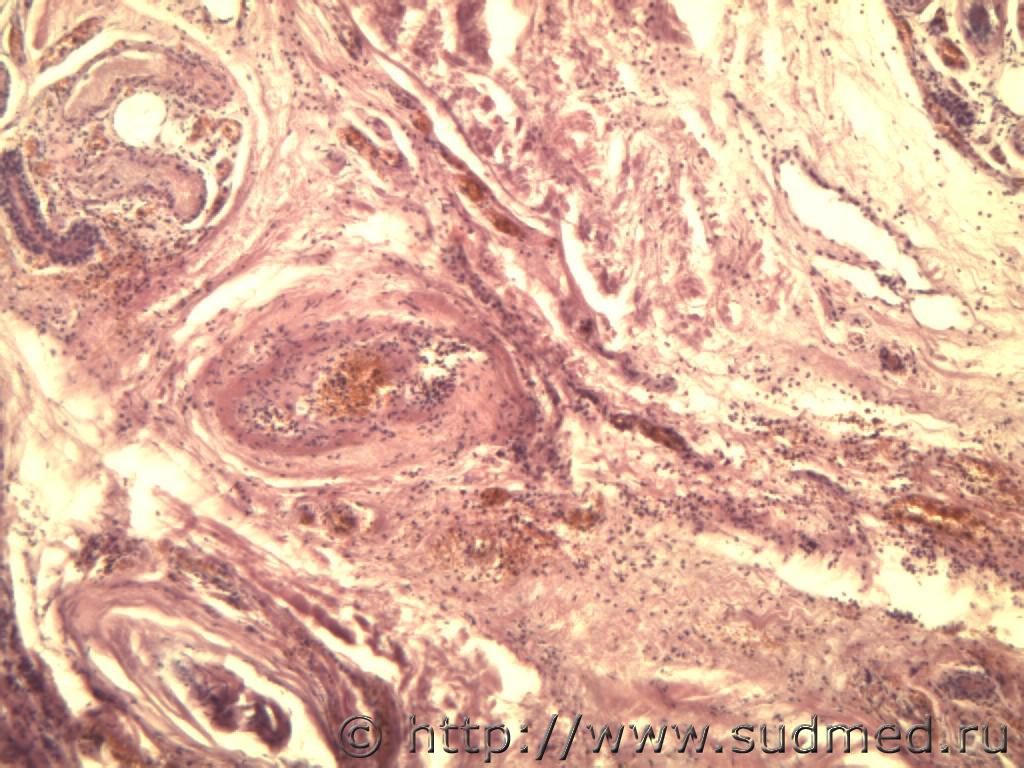

Шовный материал в стенке толстой кишки.Операция 7 лет назад.